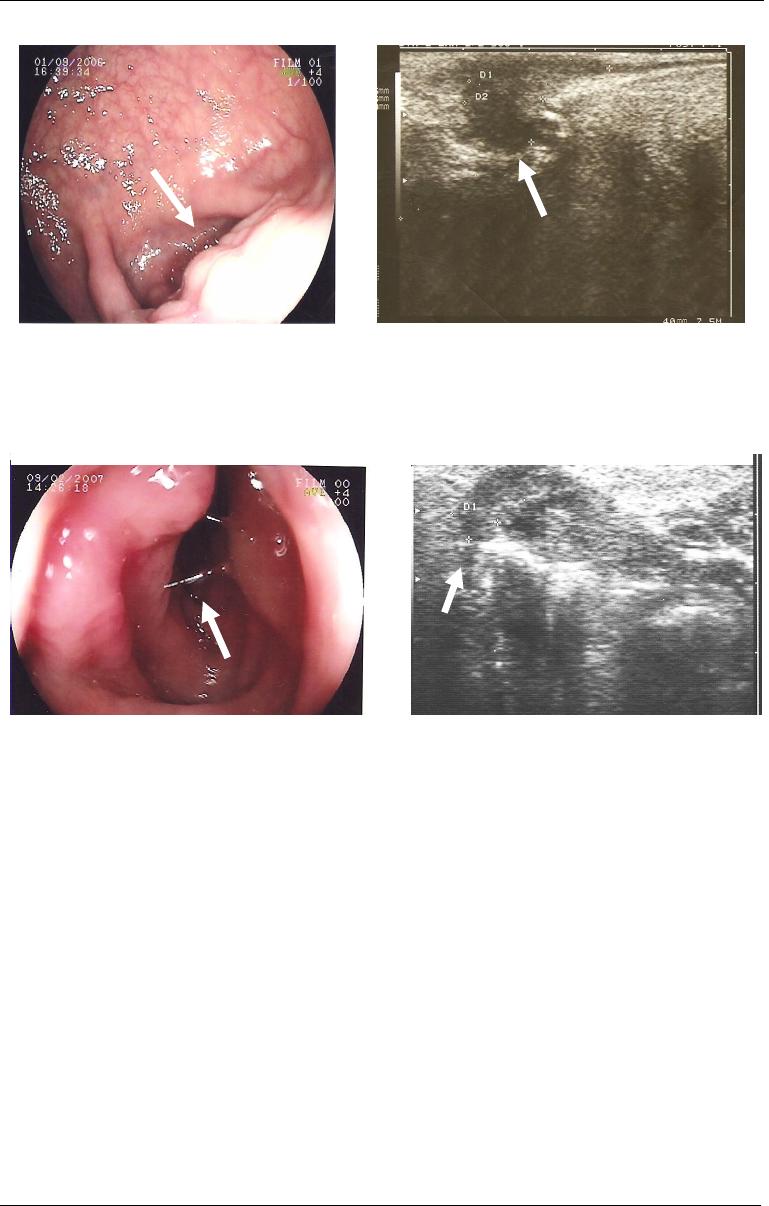

Figu

ra

1

2

- Imagem de endossonografia intestinal

(sete e meio megahertz) evidenciando-se, em corte

sagital da pelve, espessamento hipoecogênico (seta)

correspondente a nódulo de endometriose do reto

aderido à parede posterior do útero, caracterizando

ecograficamente o bloqueio do recesso retro-uterino.

Obs: Imagem cedida pelo Dr. Lucio Rossini.

Figura

13

sagital do reto e do canal anal, espessamento

hipoecogênico (seta para a direita) correspondente

a nódulo de endometriose do reto, com afilamento

até seu término (seta amarela para cima). Observa-

se, também, início do espessamento da camada

muscular própria do reto, que corresponde ao

começo do esfíncter interno do ânus (seta branca

para cima). Utilizando dispositivo de mensuração

de distâncias do aparelho de ecografia, podemos

determinar em milímetros a distância entre a lesão

e o esfíncter interno do ânus. Obs: Imagem cedida

pelo Dr. Lucio Rossini.

Ecograficamente, a endometriose aparece como lesões hipoecogênicas,

arredondadas ou triangulares, localizadas adjacentes e anteriormente e/ou

lateralmente ao reto. A infiltração da parede é definida quando ocorre espessamento

da camada muscular própria intestinal (Chapron et al, 2004) (Figuras 12 e 13).